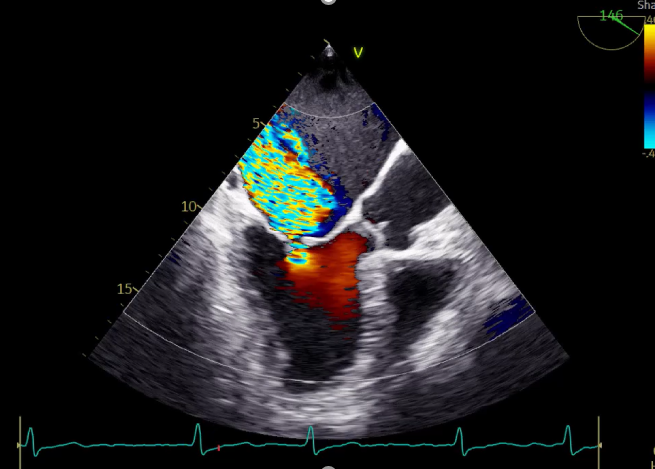

造影提示微少量返流,压力监测提示主动脉瓣压差7mmHg

LVOT-color:MR(重度),返流面积11.3cm2

患者麻醉方式为全麻,建立静脉通路后,穿刺右侧股静脉,预埋ProGlide缝合器,食道超声指导下房间隔穿刺成功,将Superstiff导丝送至左房,应用18F鞘管扩张穿刺部位,沿导丝将导引导管送入左房,MitraClip调整后顺利到达二尖瓣目标位置,在X线及食道超声辅助下,将Mitraclip NTR成形夹精确定位后,成功夹合二尖瓣A2-P2区,超声显示反流明显减少,多切面证实夹合组织充分,肺静脉多普勒波形由反向恢复正常,手术顺利结束,安返普通病房。

3D-color:残余少量返流